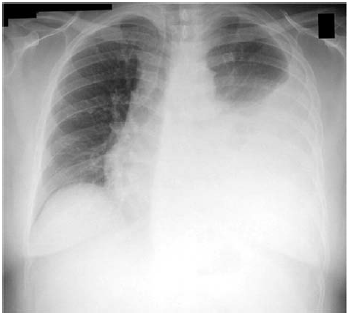

Certo paciente de 25 anos de idade sofreu uma queda de moto

há 45 dias, com atendimento no hospital de pronto-socorro. Ele

foi diagnosticado com hemotórax, teve o tórax drenado na

ocasião e retirou-se o dreno no quinto dia, após resolução

completa do quadro. O paciente, então, retornou com dor

torácica ventilatória dependente à direita, febre e tosse com

escarro mucopurulento. Depois da avaliação inicial, raios X

foram solicitados, os quais estão disponíveis na imagem a

seguir.

No que concerne a esse caso clínico hipotético, e considerando a imagem radiográfica apresentada, assinale a alternativa que indica, respectivamente, a hipótese diagnóstica e o tratamento para esse paciente.